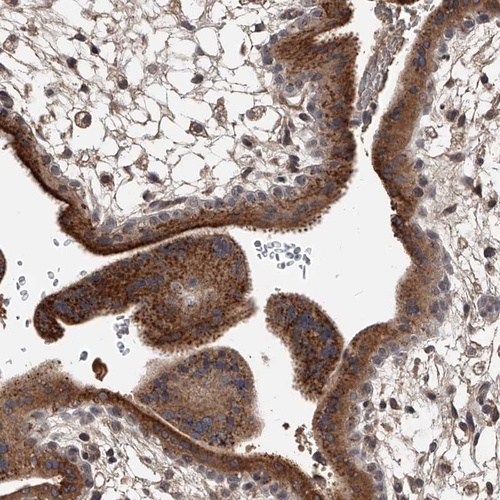

Immunohistochemical staining of human placenta shows strong cytoplasmic positivity in trophoblastic cells.